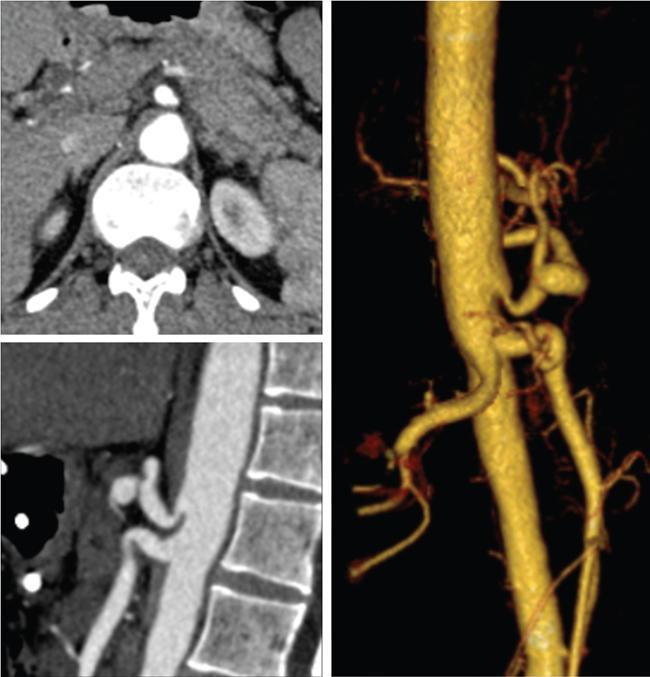

Computed tomography

CT enterography